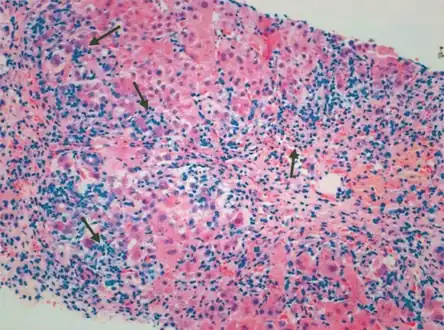

| Micrograph showing a lymphoplasmacytic interface hepatitis—the characteristic finding of autoimmune hepatitis. Liver biopsy. H&E stain. | |

Portal and periportal inflammatory infiltrate- interface hepatitis (piecemeal necrosis) arrow(s)